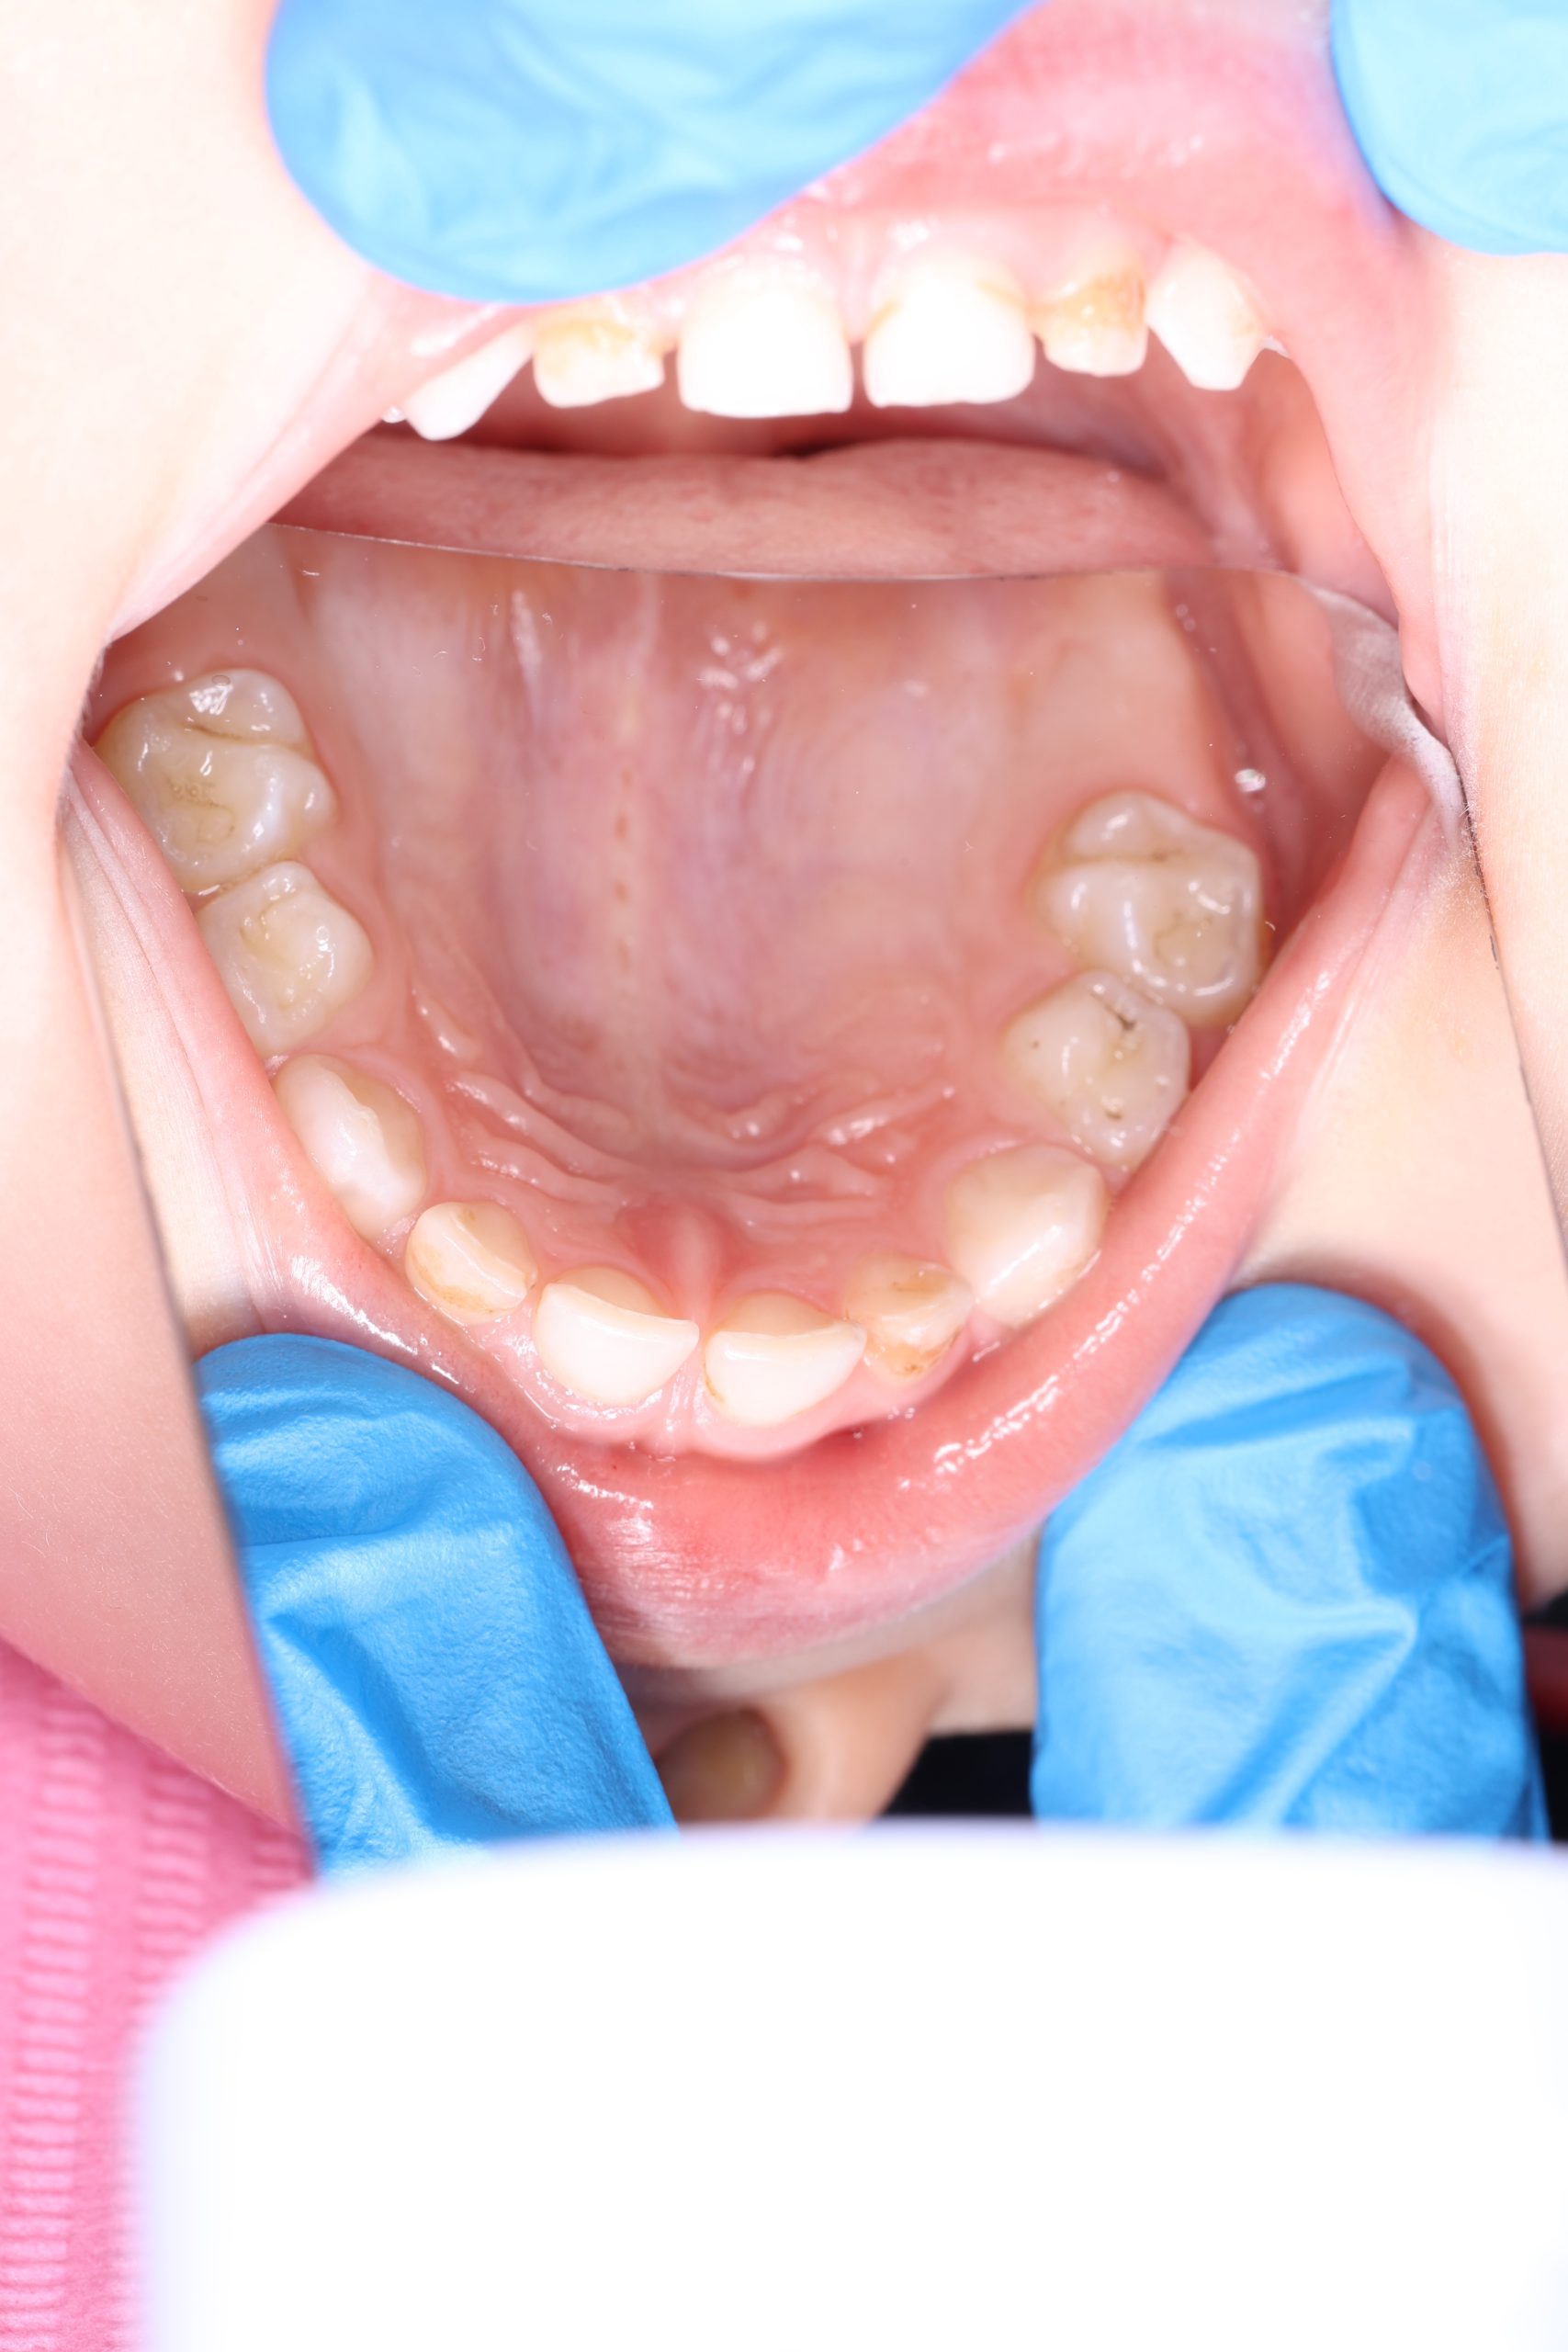

We examine the condition of teeth, gums, and bite. - Plaque Disclosure with Special Indicators

Areas that weren’t cleaned well appear purple. The darker the shade, the older the plaque. This helps both kids and parents understand where brushing needs to improve. - Brushing Training & Home Care Tools Selection